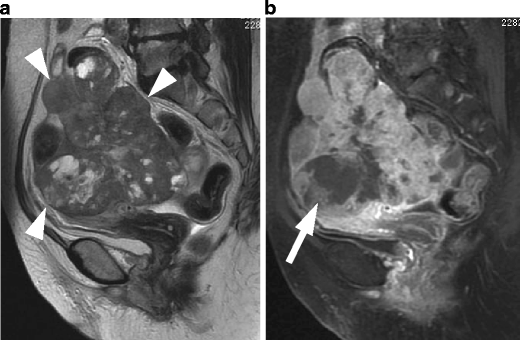

Undifferentiated stromal sarcoma in a 22-year-old female who presented with acute abdomen due to uterine rupture. a Sagittal T2-weighted image demonstrates an ill-defined myometrial mass of heterogeneous appearance in the anterior wall (arrows). The upper portion of the tumor containing fluid-fluid level represents hemorrhagic necrosis within the tumor (arrowheads). b T1-weighted image demonstrates increased signal intensity corresponding to the area of hemorrhagic necrosis (arrowheads). Hemorrhagic ascites of increased signal intensity also is present in the Douglas fossa and uterovesical fossa (asterisks). c Postcontrast T1-weighted image with fat suppression demonstrates heterogeneous enhancement within the solid component of the tumor (arrows)